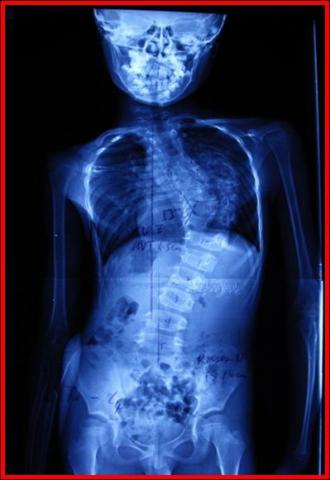

回顾文献,有关先天性脊柱侧弯合并脊髓纵裂的自然发展史未见报道。考虑到脊髓纵裂可能终身无症状,沈建雄教授等通过循证医学论证,在国际上较早提出,对未出现神经症状或神经症状稳定的患者,无需一律预防性切除骨嵴或纤维膜,可一次性行脊柱侧弯矫形手术的做法。2000年,骨科在对患者进行脊柱侧弯型、神经功能等详细术前评估的基础上完成了第一例单纯脊柱侧弯矫形术。

截止2010年11月,北京协和医院骨科对124例明确诊断为先天性脊柱侧弯合并脊髓纵裂、且未出现神经症状或神经症状稳定期大于两年的患者行单纯矫形术。并对其中73例患者进行了2年以上随访,平均随访时间为5.3年,所有患者术后矫形均在50%以上,且无一例发生神经系统并发症。以上数据表明协和骨科所行单纯脊柱侧弯矫形手术安全、有效。